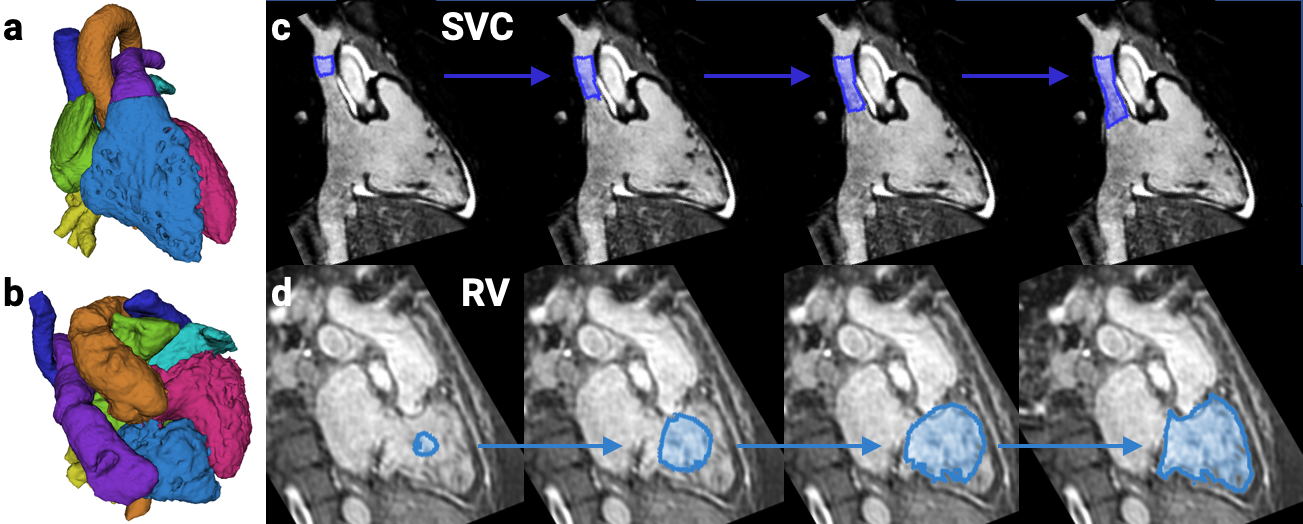

We are working on segmenting the cardiac chambers and great vessels from 3D MRI, for patients with congenital heart disease. The aim is to enhance surgical planning via rendered or 3D-printed heart models.

We have previously developed a recurrent neural network (RNN) model that evolves a segmentation of each structure over time, and shown that it is more generalizable to severe CHD defects than conventional models that segment the image in one step.

Iterative segmentation from limited training data: Applications to congenital heart disease

D.F. Pace, A.V. Dalca, T. Brosch, T. Geva, A.J. Powell, J. Weese, M.H. Moghari, P. Golland MICCAI Workshop on Deep Learning in Medical Image Analysis, 2018